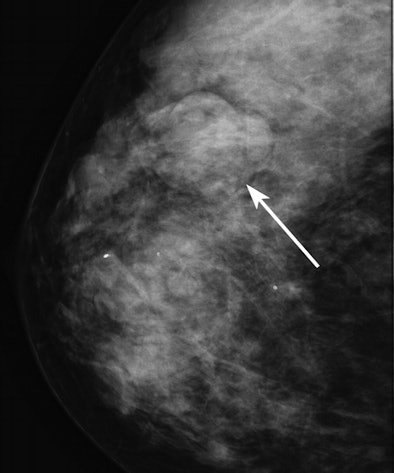

![]() |

| Mammographic image of an isodense mass (arrow). |